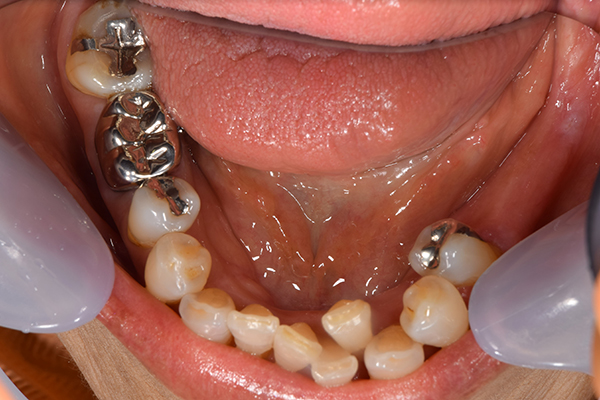

上下の入れ歯が外れやすくなったということでいらっしゃいました。 顎の骨はしっかりしていましたので、精密な型取りさえすればしっかりした入れ歯がつくれると思いました。 また下には6本歯が残っていましたが、虫歯になっている歯もありました。 かぶせ物のなかで大きな虫歯があった歯があり、1本だけ残せない状態でした。

上の入れ歯は確かに吸着は甘くなっていました。 また下の入れ歯はバネの一部が壊れており、安定感がなくなっていました。

下の入れ歯